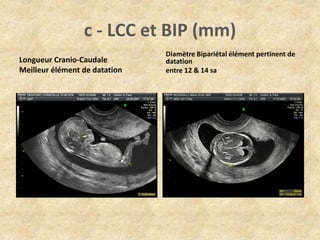

c - LCC et BIP (mm)

Longueur Cranio-Caudale

Meilleur élément de datation

Diamètre Bipariétal élément pertinent de

datation

entre 12 & 14 sa

c - LCCet BIP (mm) Longueur Cranio-Caudale Meilleur élément de datation Diamètre Bipariétal élément pertinent de datation entre 12 & 14 sa